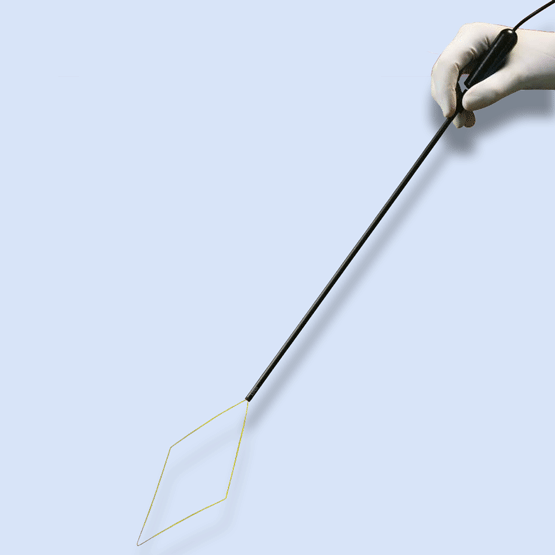

LiNA GoldLoop HC™

| EL-160-4 | 5mm Monopolar Endoscopic Loop for Laparoscopic Supracervical Hysterectomy & Myomectomy. Dimensions of loop: 160mm x 80mm. With 3 meter cable and 4mm ESU connector. | Box of 6, sterile, single use |

| EL-160-8 | 5mm Monopolar Endoscopic Loop for Laparoscopic Supracervical Hysterectomy & Myomectomy. Dimensions of loop: 160mm x 80mm. With 3 meter cable and 8mm ESU connector. | Box of 6, sterile, single use |

| EL-200-4 | 5mm Monopolar Endoscopic Loop for Laparoscopic Supracervical Hysterectomy & Myomectomy. Dimensions of loop: 200mm x 100mm. With 3 meter cable and 4mm ESU connector. | Box of 6, sterile, single use |

| EL-200-8 | 5mm Monopolar Endoscopic Loop for Laparoscopic Supracervical Hysterectomy & Myomectomy. Dimensions of loop: 200mm x 100mm. With 3 meter cable and 8mm ESU connector. | Box of 6, sterile, single use |

| EL-240-4 | 5mm Monopolar Endoscopic Loop for Laparoscopic Supracervical Hysterectomy & Myomectomy. Dimensions of loop: 240mm x 120mm. With 3 meter cable and 4mm ESU connector. | Box of 6, sterile, single use |

| EL-240-8 | 5mm Monopolar Endoscopic Loop for Laparoscopic Supracervical Hysterectomy & Myomectomy. Dimensions of loop: 240mm x 120mm. With 3 meter cable and 8mm ESU connector. | Box of 6, sterile, single use |